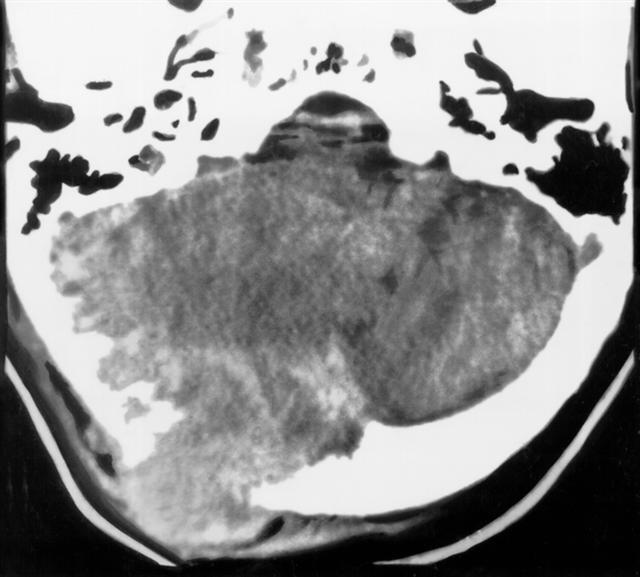

Рис. 12. Аксиальная компьютерная томограмма при метастазе аденокарциномы почки в чешую затылочной кости: справа видна локальная деструкция кости, интракраниальные узлы опухоли и в прилежащих мягких тканях головы.